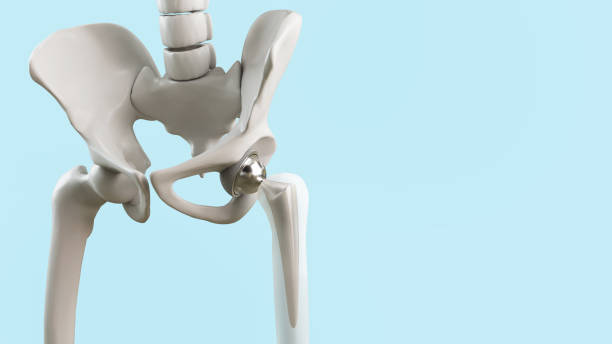

고관절 통증을 관리하고 치료하기 위해서는 다양한 요인을 고려해야 합니다. 통증을 완화하고 원인을 해결하기 위해 개별 환자에게 맞춤형 치료 계획이 필요합니다. 이때, 관절과 근육의 조화로운 기능을 회복시키기 위한 재활운동이 중요합니다.

고관절 통증을 피하기 위해서는 예방이 중요합니다. 특히, 허리와 고관절을 지지하는 근육을 강화하는 운동은 큰 도움이 됩니다. 이러한 운동은 40대부터 시작하여 허리와 관절의 건강을 유지하는 데 도움을 줄 수 있습니다.